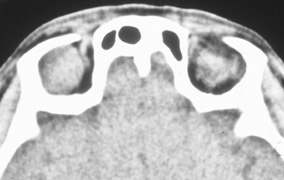

The transcranial orbitotomy uses a frontal craniotomy with removal of a portion of the orbital roof to expose the orbital apex or superior orbit. This is best performed by a neurosurgeon familiar with skull-base surgical approaches. In most cases, the supraorbital rim over the involved side is removed en bloc with the frontal bone flap (Fig. 13). The anterior one-half or two-thirds of the orbital roof breaks free with removal of the rim and frontal bone flap, and the remaining posterior portion of the roof can be removed with rongeurs. Historically, it was suggested that all orbital tumors be removed via craniotomy, because before the imaging era it was difficult to anticipate the intraorbital location of a mass.18 The transfrontal approach was first described by Jones10 in 1970. Jane and colleagues19 proposed the current technique in 1982. Refinements have been discussed by Maroon and Kennerdell9 and Housepian.20 This operation has been termed the panoramic orbitotomy by Rootman21 because of the wide area of exposure offered by this procedure.

Fig. 13. Schematic diagram for transcranial orbitotomy in which the supraorbital rim is removed en bloc with the frontal bone flap. This provides extensive exposure to the superior and lateral orbit.